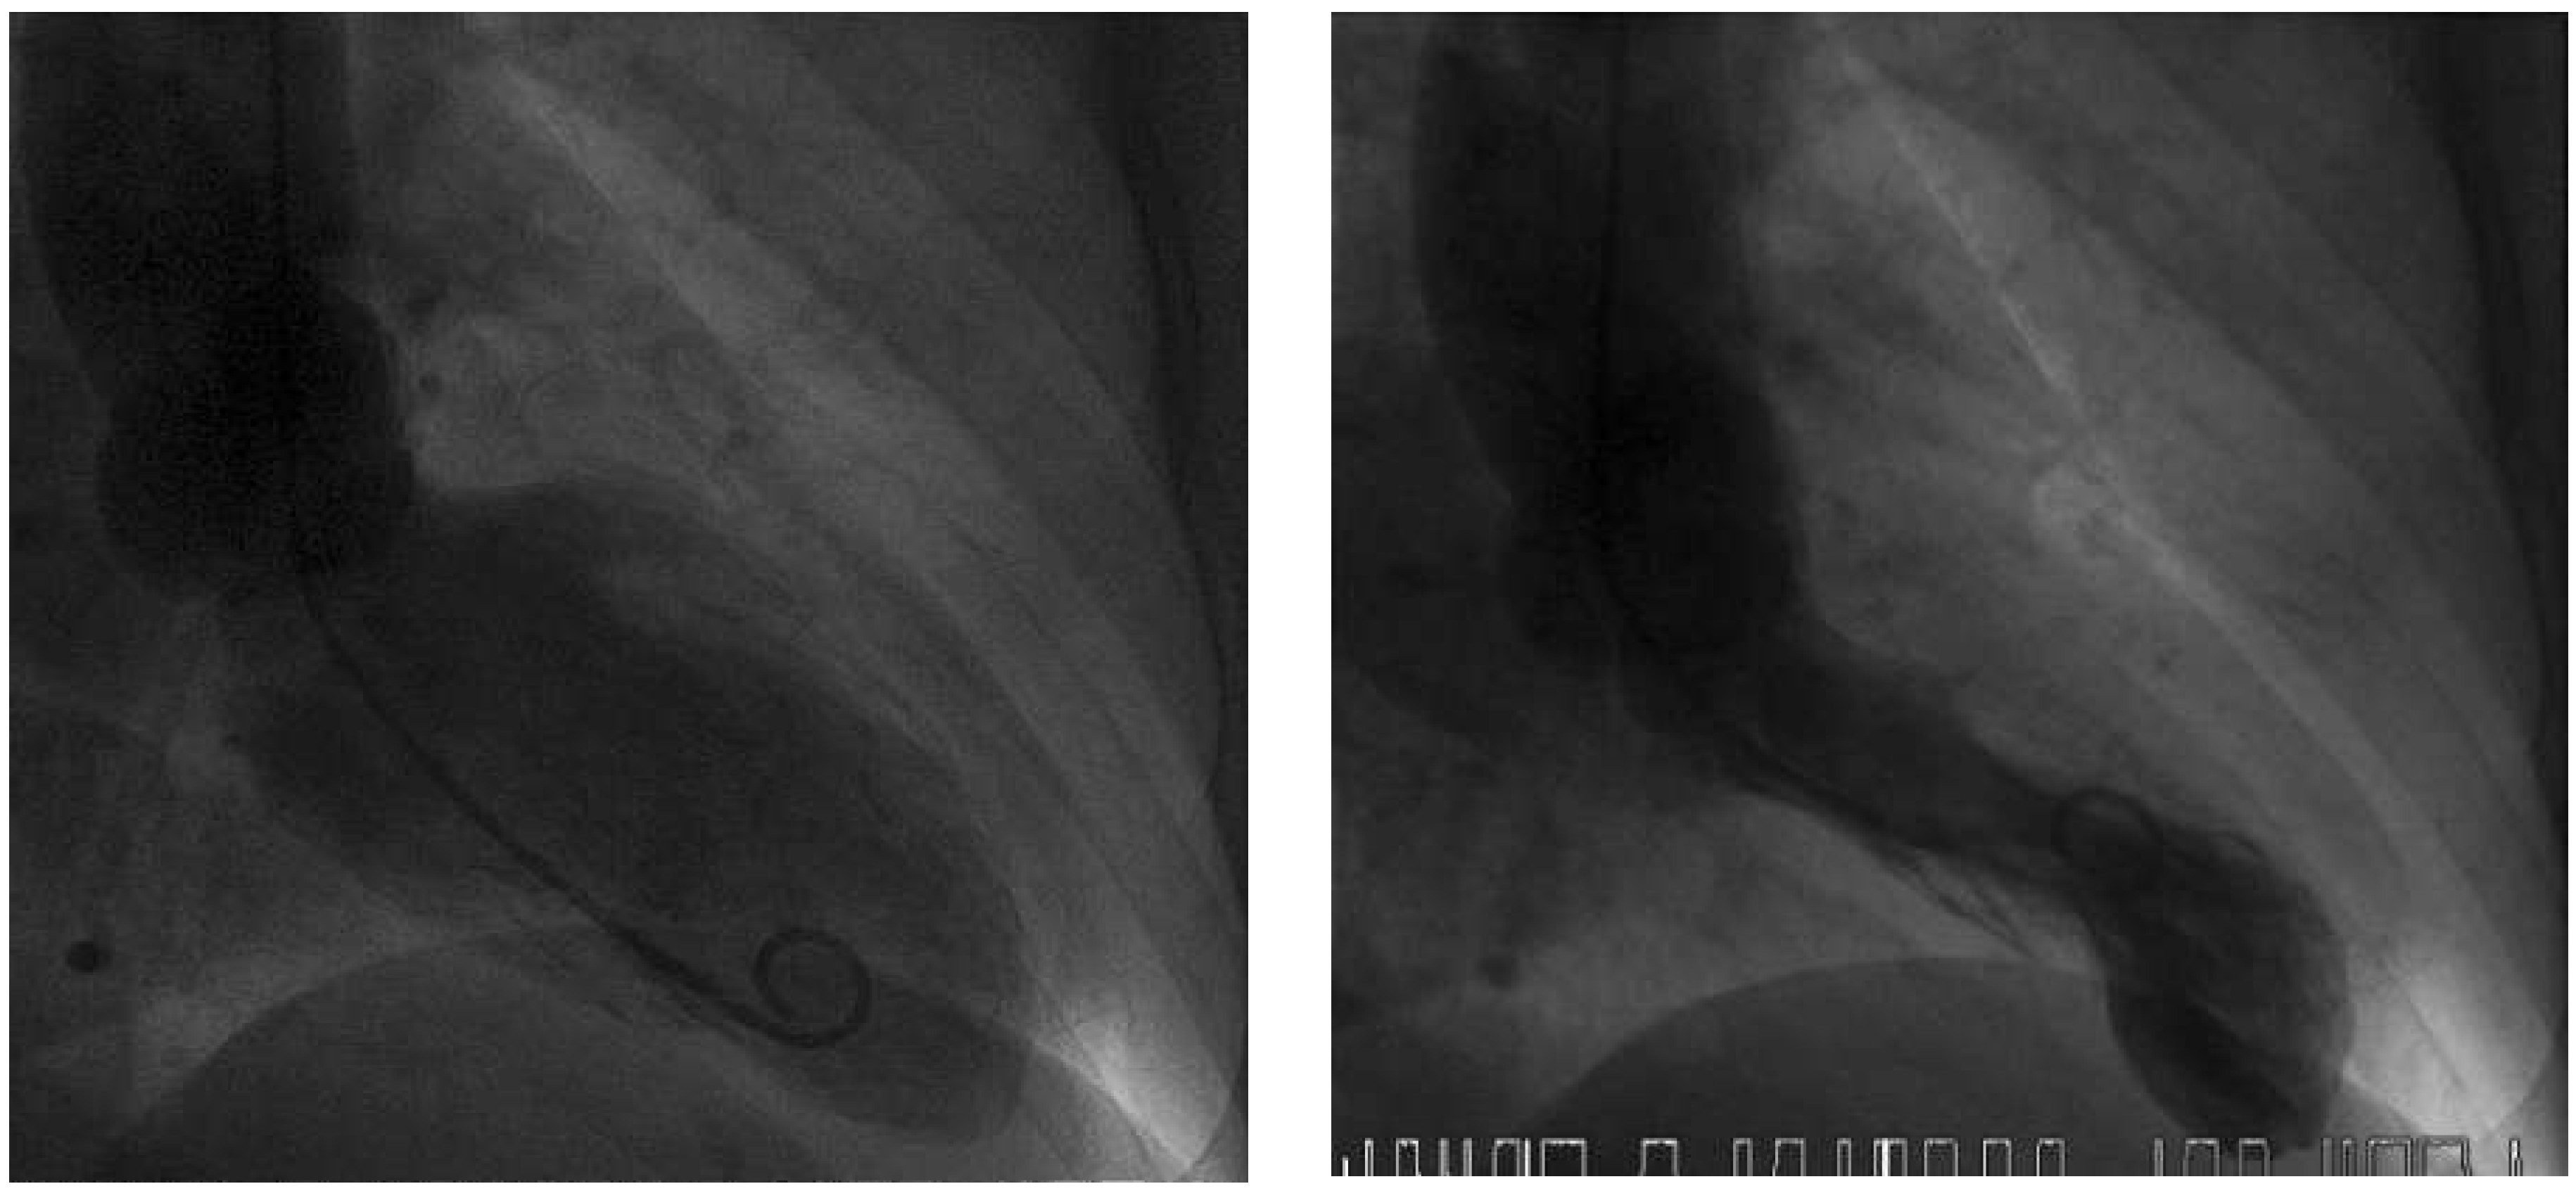

Figure 3. Left ventriculogram with end-diastolic (left) and endsystolic (right) frames.Systolic apical ballooning suggests takotsubo syndrome.